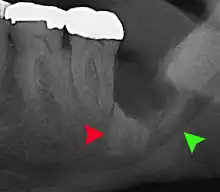

| 3D CT of an impacted wisdom tooth adjacent the inferior alveolar nerve prior to removal of wisdom tooth | |

Long-term complications can include periodontal complications such as bone loss on the second molar following wisdom teeth removal. Bone loss as a complication after wisdom teeth removal is uncommon in the young but present in 43% of those of 25 years of age or older.[22] Injury to the inferior alveolar nerve resulting in numbness or partial numbness of the lower lip and chin has reported rates that vary widely from 0.04% to 5%.[22] The largest study is from a survey of 535 oral and maxillofacial surgeons in California, where a rate of 1:2,500 was reported.[25]

Coronectomy

Coronectomy is a procedure where the crown of the impacted wisdom tooth is removed, but the roots are intentionally left in place. It is indicated when there is no disease of the dental pulp or infection around the crown of the tooth, and there is a high risk of inferior alveolar nerve injury.[31]

Coronectomy, while lessening the immediate risk to the inferior alveolar nerve function has its own complication rates and can result in repeated surgeries. Between 2.3% and 38.3% of roots loosen during the procedure and need to be removed and up to 4.9% of cases require reoperation due to persistent pain, root exposure or persistent infection. The roots have also been reported to migrate in 13.2% to 85.9% of cases.[31]